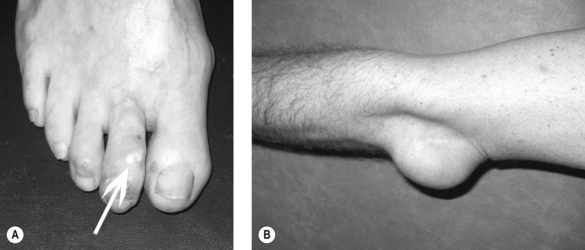

Clinical gout is sub-divided into acute gouty arthritis, interval (intercritical) gout and chronic tophaceous gout. Acute gouty arthritis typically manifests as acute mono-arthritis characterised by severe pain with associated redness, warmth, swelling and tenderness. The first metatarsophalangeal (MTP) joint is affected most frequently followed by the mid-foot, ankle, knee, finger interphalangeal joints, wrist and elbow. Attacks occur rapidly, often overnight, peaking within 24 hours, before resolving completely over a 2–3 week period. A variable period elapses before the next attack occurs (interval gout). With time, attacks become more frequent, more severe and are more often pauci- or polyarticular leading to chronic tophaceous gout characterised by chronic arthropathy and chalky-white subcutaneous deposits of MSU crystals (tophi). Typical sites for tophi include the toes (Fig. 23.1A), Achilles’ tendons, fingers, elbows (Fig. 23.1B) and, less commonly, the helix of the ear.

image

Figure 23.1 Tophaceous deposits of subcutaneous monosodium urate crystals on (A) the right 2nd toe (white arrow) and (B) elbow.